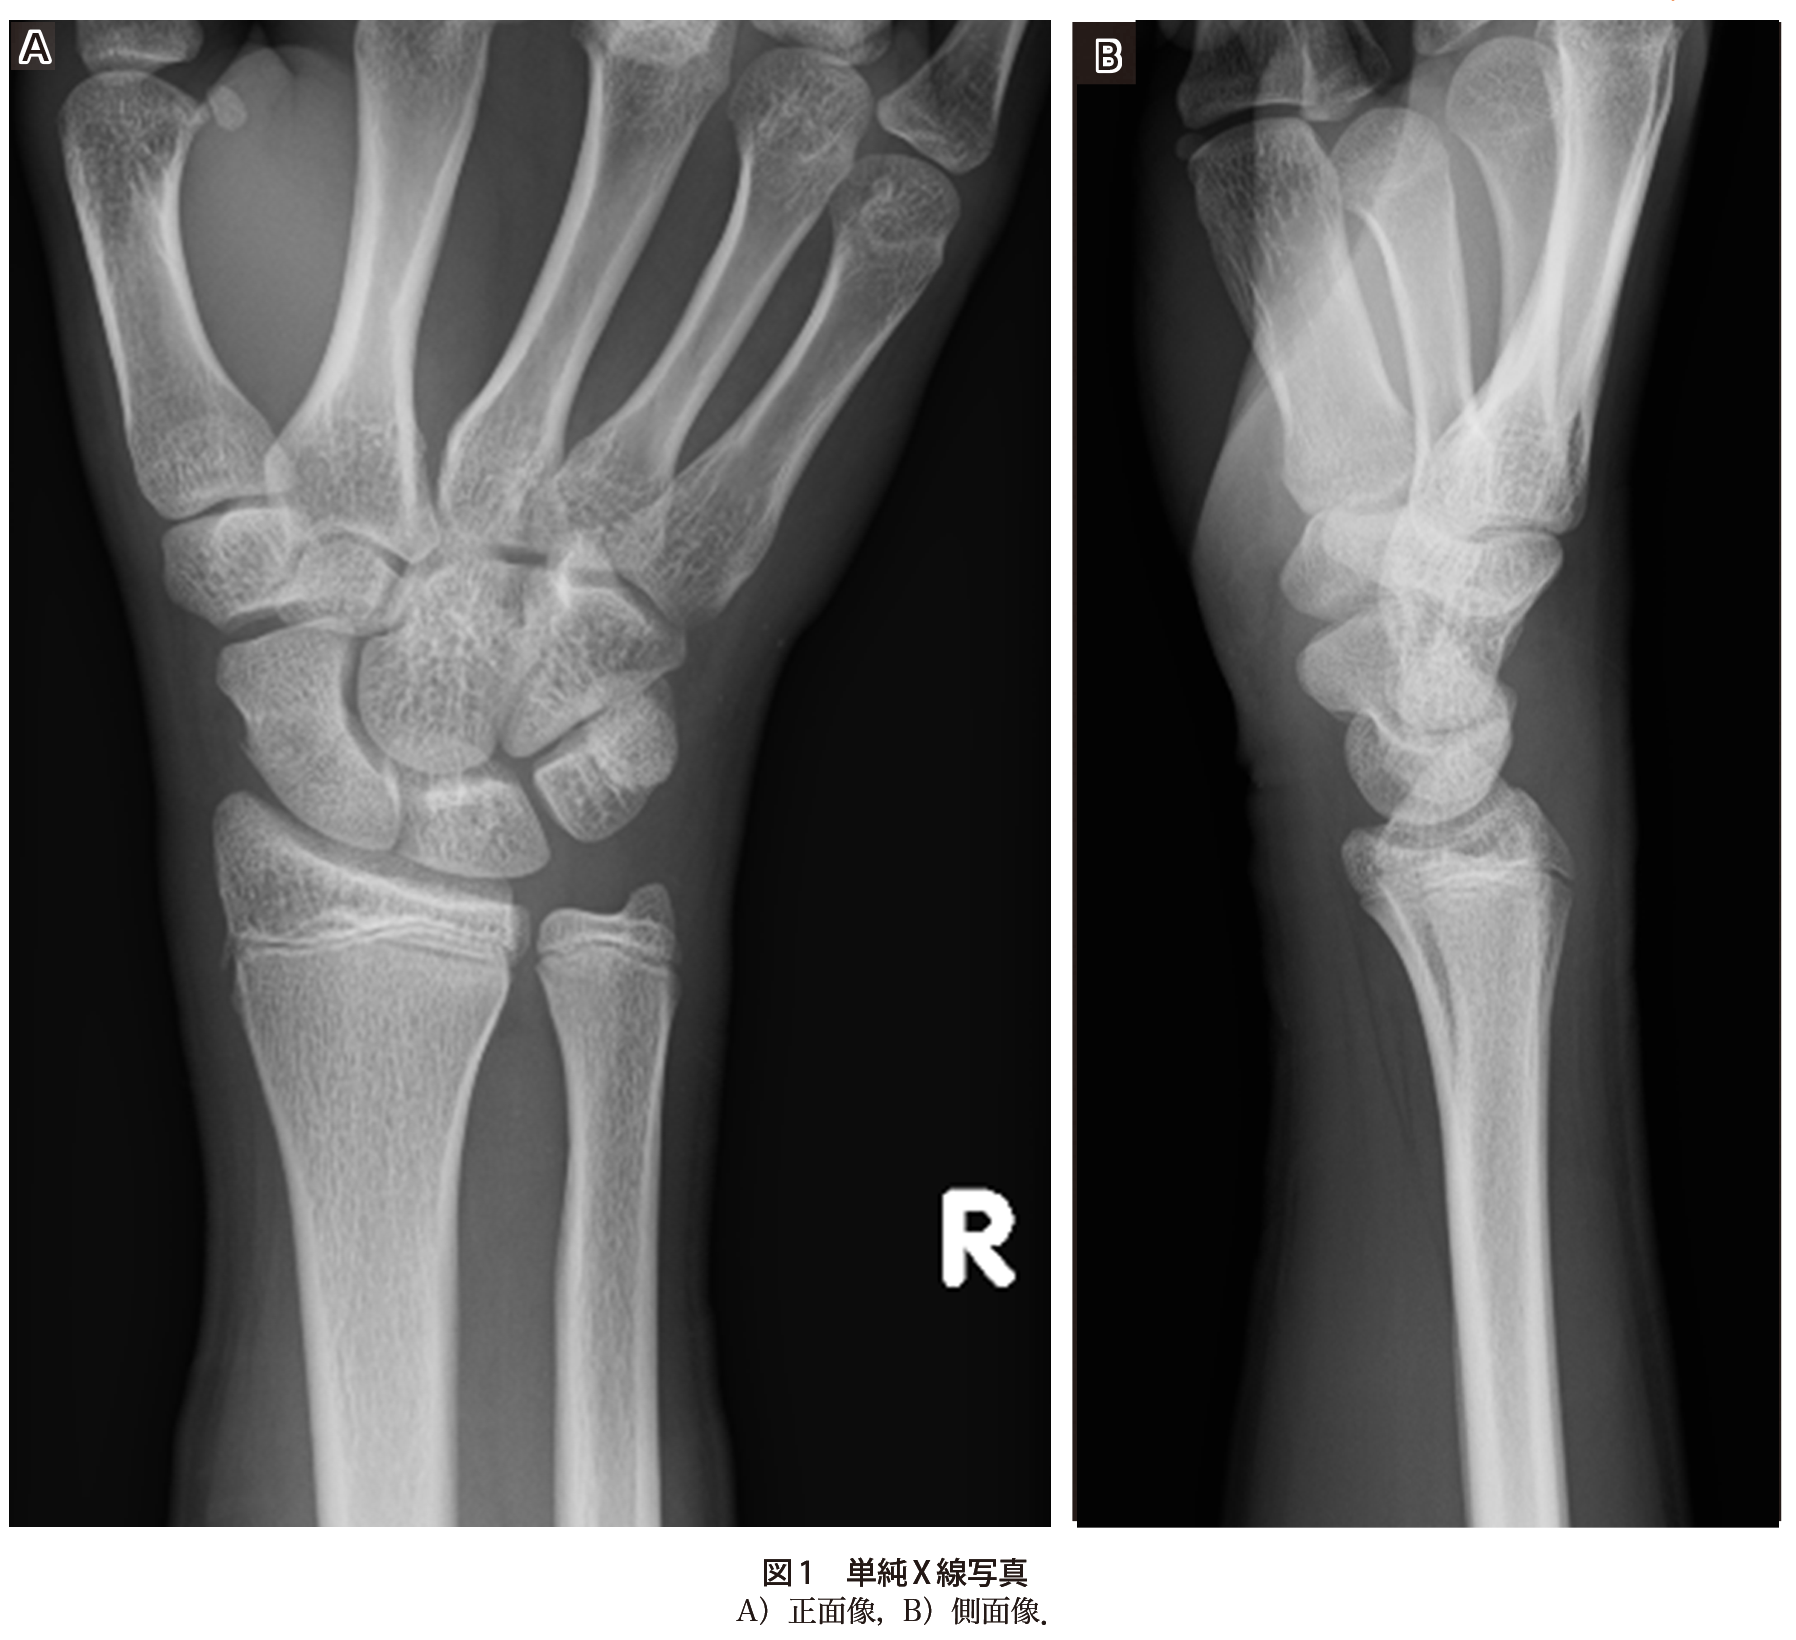

転倒後の手関節痛で来院した10歳代男性 実践 画像診断q A 羊土社 レジデントノート 羊土社